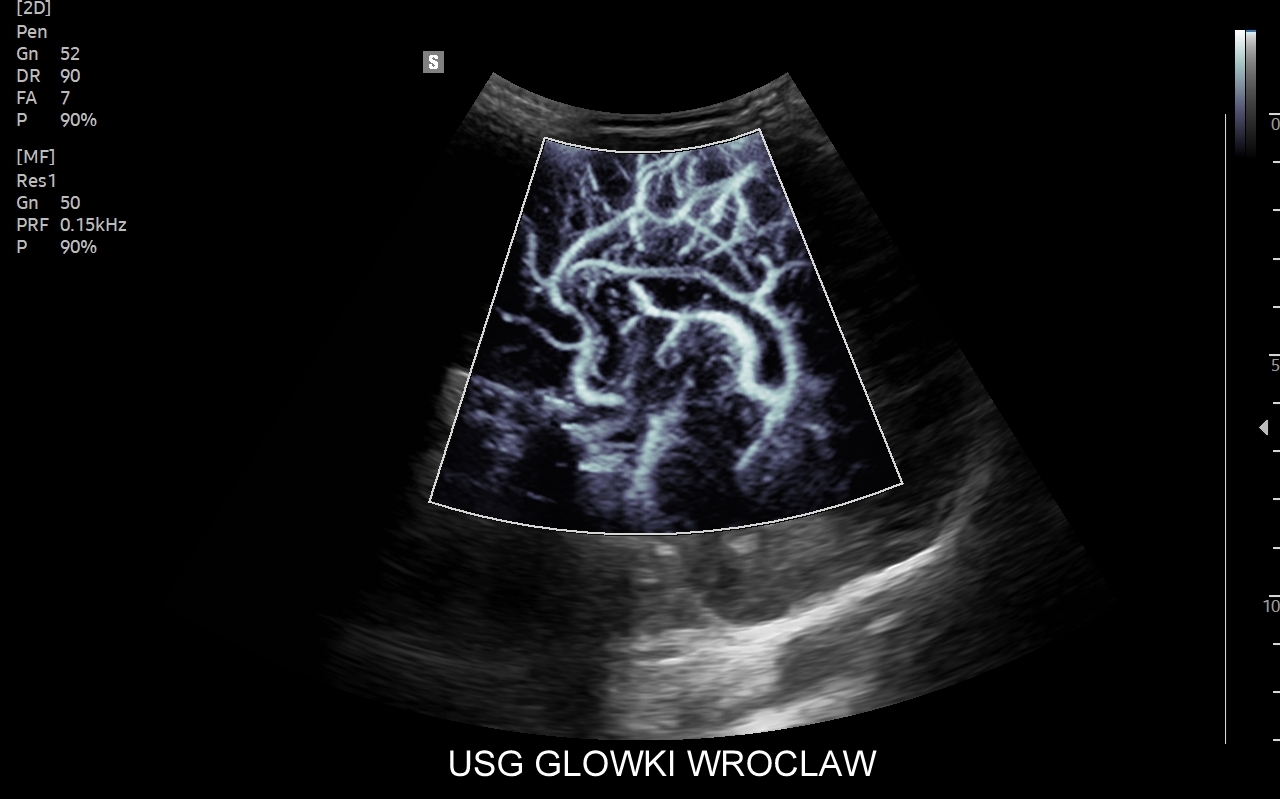

• ocenę mikrounaczynienia tkanek i narządów,

• zastosowanie angiografii sonograficznej,

• badania USG przezczaszkowe / transkranialne,

• pełen przekrój badań dopplerowskich.